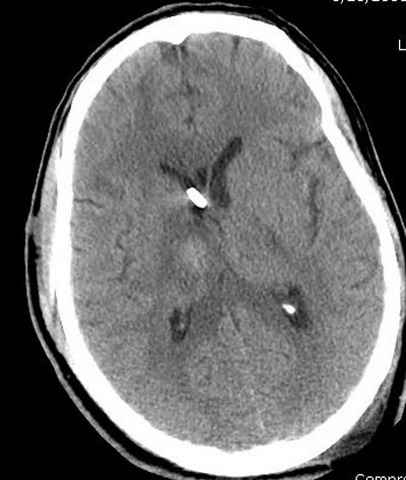

Наблюдается службой травмы и нейрохирургии (ICP) Increased Intracranial Pressure by ventricular cateter

постоперационные

монииторинг